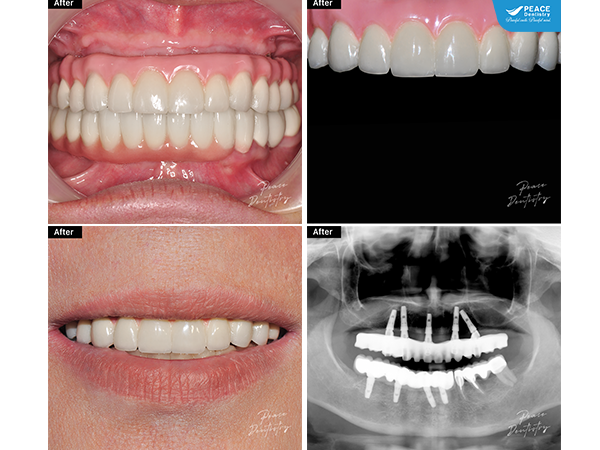

Trồng răng Implant toàn hàm All-On-5 hàm trên và All-On-4 hàm dưới

(Trồng răng Implant toàn hàm All-On-5 hàm trên và All-On-4 hàm dưới, kết hợp bọc sứ răng hàm dưới, giúp khắc phục tình trạng mất răng). Xem chi tiết ca lâm sàng tại đây (**)